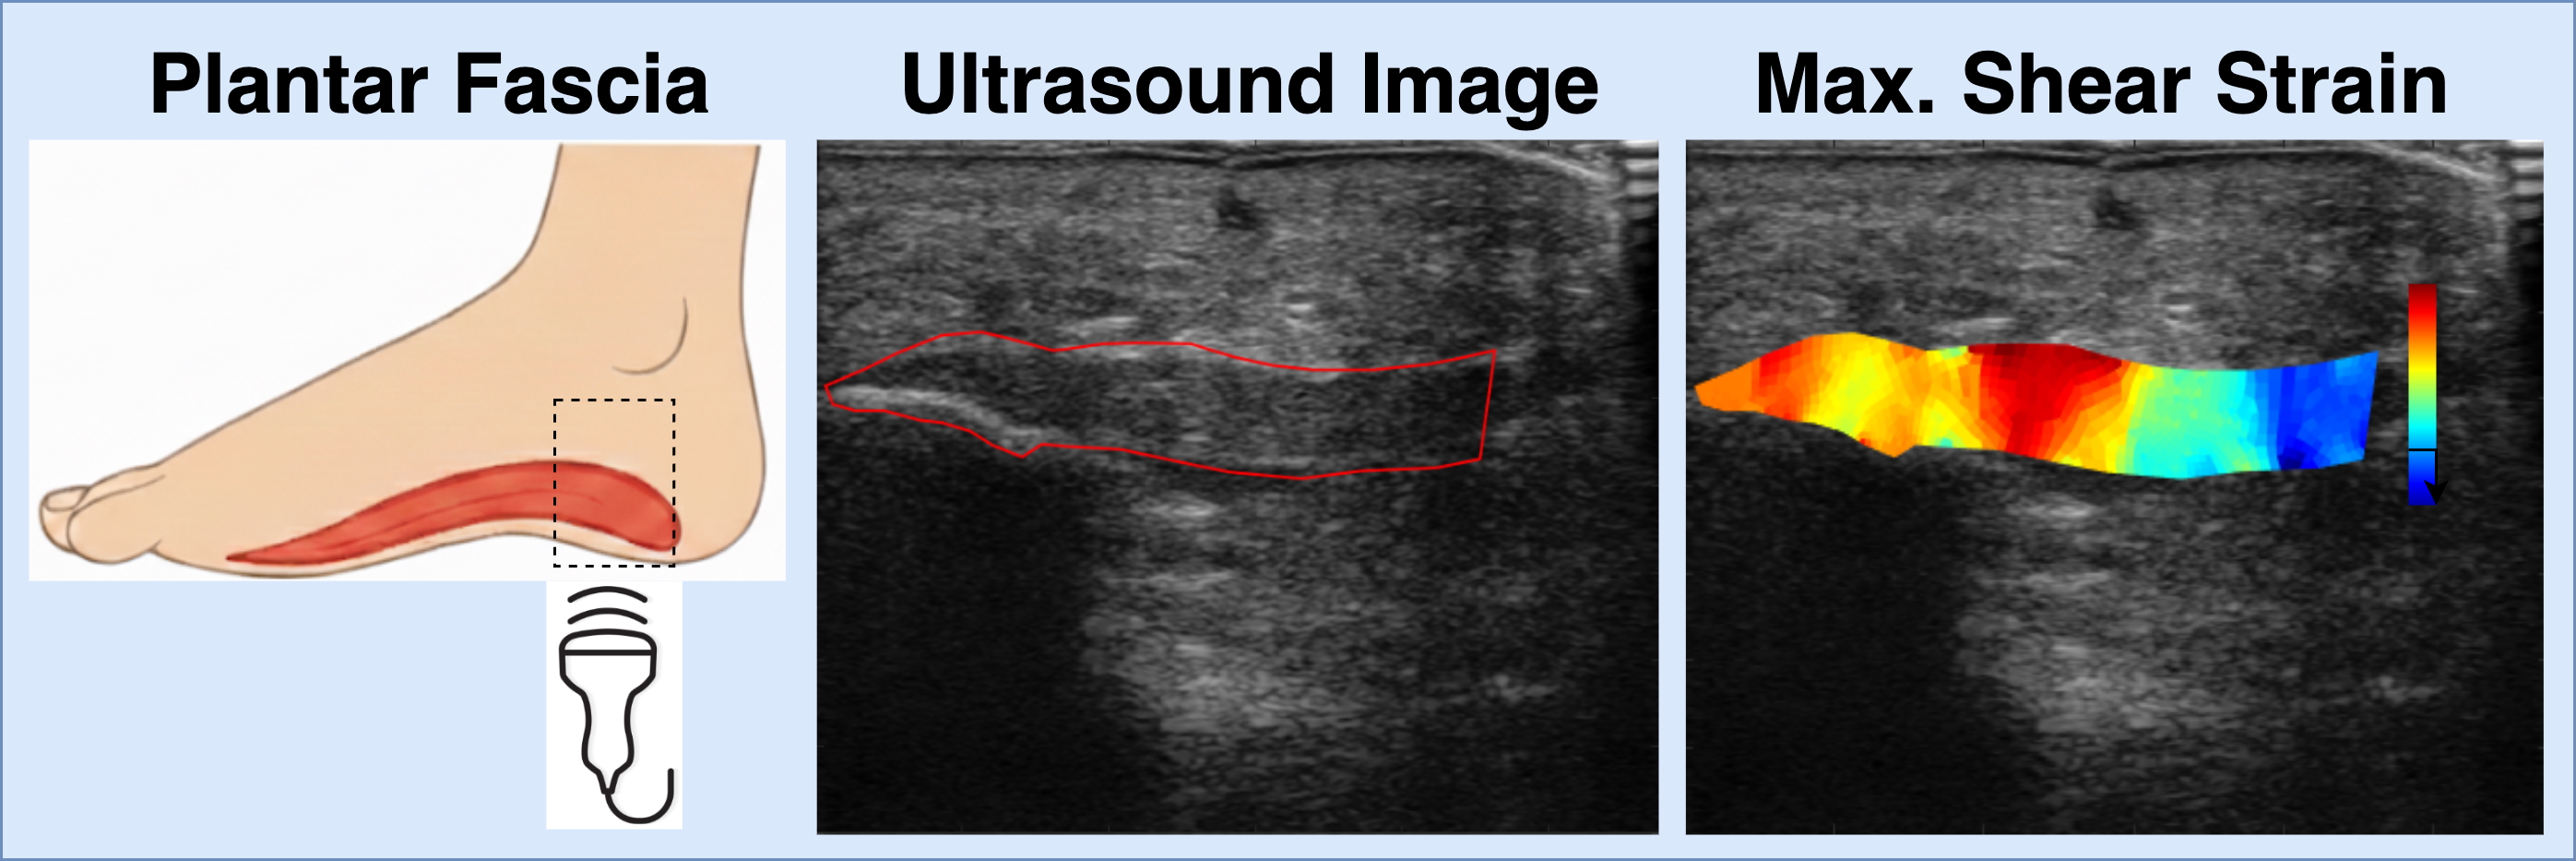

Development of Diagnostic and Prognostic Ultrasound Imaging Biomarkers for Plantar Heel Pain

Myofascial pain is a common but often underdiagnosed source of musculoskeletal pain. One of the challenges in treating it effectively is the lack of objective tools, or biomarkers, that can detect abnormal tissue and guide personalized treatment. As part of a larger study run out of the University of Iowa, our lab is focused on developing ultrasound-based BMI methods for imaging biomarkers of myofascial pain, with plantar fasciitis as a model. We hypothesize that quantifying the shear strain surrounding the plantar fascia and comparing these values across patients with plantar fasciitis, Achilles tendinopathy, and pain-free controls, we can detect a potential image-based biomarker of abnormal myofascial tissue. Using 2D ultrasound and image registration techniques, we can measure the shear strain within the plantar fascia during controlled exercise. Our goal is to provide a simple, non-invasive way to detect abnormal myofascial tissue and track changes to the tissue with treatment. Ultimately, our goal is to improve musculoskeletal pain management by giving clinicians better imaging tools to diagnose pain mechanisms and tailor therapies for each patient.